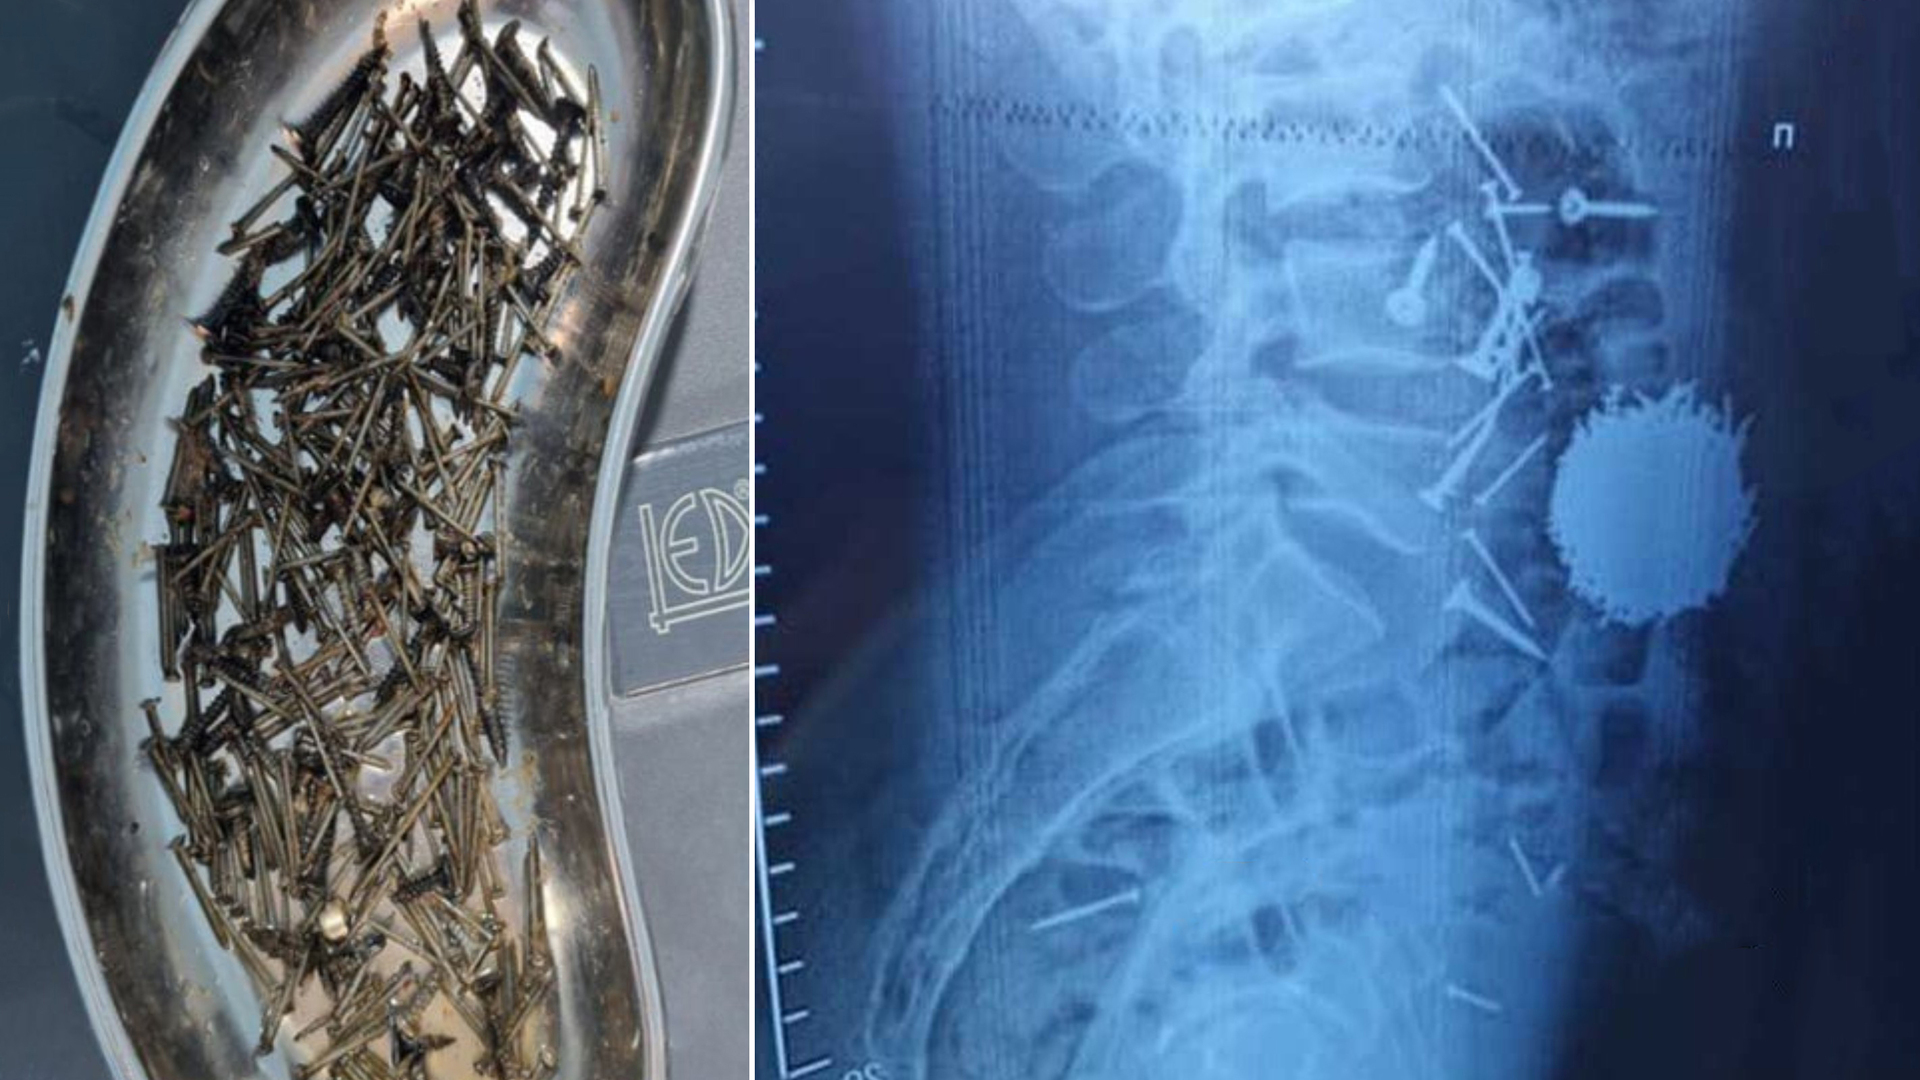

В Самарканде врачи извлекли из организма пациента почти 200 граммов гвоздей и саморезов

Выяснилось, что мужчина проглотил металлические предметы под воздействием сильного стресса.

На днях в Самаркандский филиал Республиканского научного центра экстренной медицинской помощи был госпитализирован 29-летний гражданин с сильными болями в области живота, сообщает пресс-служба медучреждения.

По результатам диагностики и лабораторных исследований у пациента в желудочно-кишечном тракте было выявлено большое количество металлических предметов — гвоздей и саморезов.

«Было принято решение о необходимости проведения экстренного хирургического вмешательства. После выполнения всех подготовительных процедур была проведена операция методом лапаротомии и гастростомии. Из брюшной полости пациента удалось извлечь значительное количество металлических предметов — около 200 граммов. Операция длилась около часа», — сообщил врач высшей категории медцентра Юлдош Кулиев.

Согласно имеющейся информации, мужчина находился под воздействием сильного стресса и, не контролируя свои действия, проглотил вышеуказанные предметы.

Отмечается также, что в настоящее время состояние пациента удовлетворительное, он может свободно передвигаться.